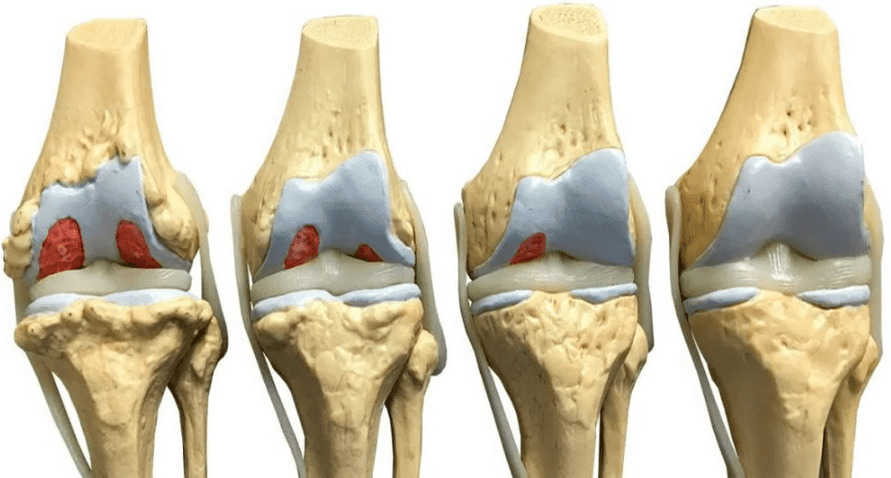

Професор Пак: У Китаї ми довели, що суглоби можуть повністю регенерувати, і їх можна і потрібно лікувати. Основна проблема хвороби - це зношування. Суглоби постійно піддаються високим навантаженням, тому хрящова тканина втрачає еластичність стоншується і зношується. Звідси біль, пухлини (грижа міжхребцевого диска) та деформація кісток (остеоартроз). До 60 років багато людей вже втратили 45-50% свого хряща. Як можна відновити те, чого вже немає? Чи можна буквально "побудувати" суглоб? Так, можна!

Кореспондент: Як виглядає процес відновлення?

Професор Пак: Доведено, що клітини, які відповідають за здоров'я та ріст хрящової тканини розташовані всередині нього.. Складники OsteoFixу не тільки знімають набряк, біль і запалення, але й безпосередньо впливають на ці клітини і активізують їх розподіл. Іншими словами, цей продукт активує сплячий механізм і змушує його працювати швидше. Засіб OsteoFix посилює кровообіг в навколишніх тканинах, що призводить до до розмноження рідини в суглобовій капсулі. Це збільшує рухливість самого суглоба і дозволяє йому прискорити зростання хрящової тканини. Що стосується злоякісних пухлин (гриж), то вони поступово пом'якшуються під впливом препарату і виводяться з організму спочатку кров’ю, а потім природним шляхом, просочуючись у кишечник.